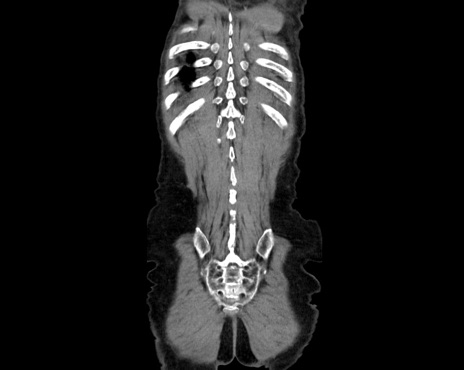

症例26(冠状断像)

【症例】80歳代男性

【主訴】嘔吐

【現病歴】昨晩2回嘔吐あり、今朝になっても嘔吐あり。来院。

【既往歴】胃潰瘍

【身体所見】意識清明、BT 37.6℃、BP 166/95mmHg、HR 100bpm、SpO2 97%、腹部:平坦・軟、腸蠕動音聴取良好、圧痛なし。

【データ】WBC 21900、CRP 1.4